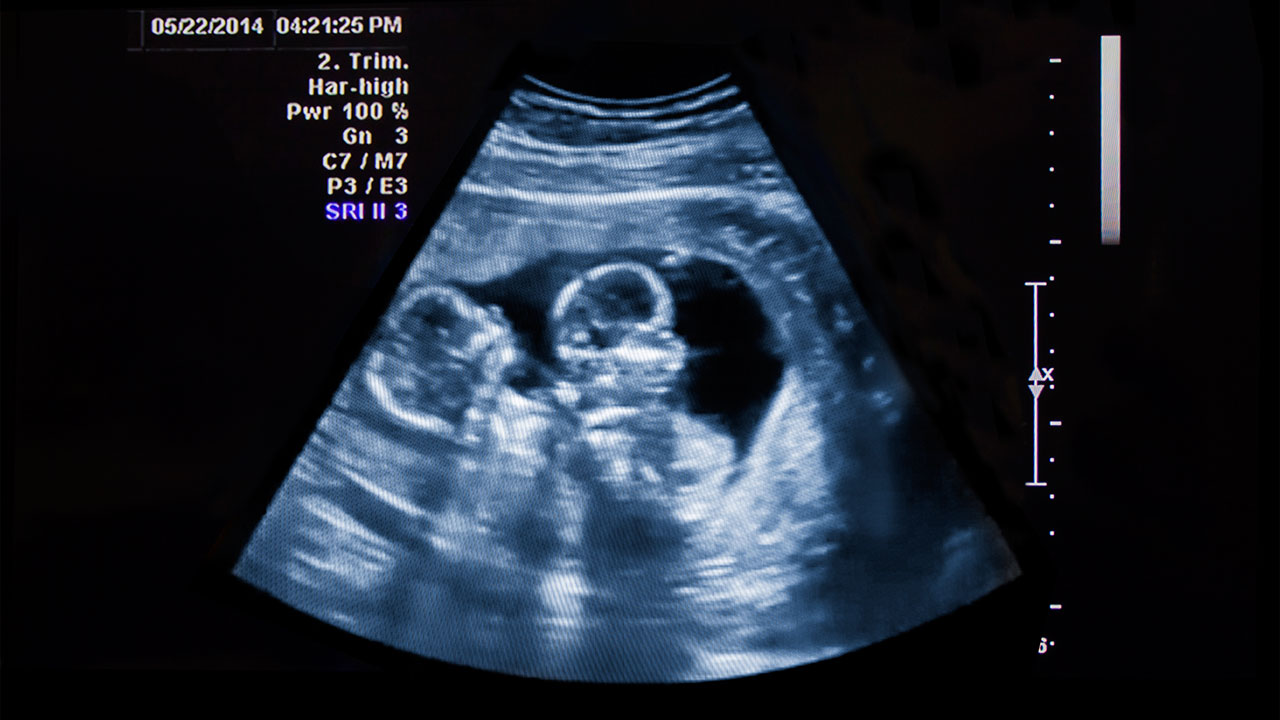

Multiple (Twins/Higher Order) Pregnancy Imaging

Multiple (Twins/Higher Order) Pregnancy Imaging is a specialized ultrasound designed to monitor the unique needs of twin or higher-order pregnancies. This advanced imaging tracks the growth and development of each fetus, evaluates the placenta, amniotic sacs, and umbilical cords, and detects complications like Twin-to-Twin Transfusion Syndrome (TTTS) or growth discrepancies. Regular scans assess cervical length, fetal well-being, and Doppler blood flow to ensure optimal health for both mother and babies. Frequent monitoring—often every 2–4 weeks—supports safer birth planning, timely interventions, and personalized care to minimize risks and improve outcomes.

Benefits of Multiple Pregnancy Imaging

Twins and higher-order pregnancies carry higher risks than singleton pregnancies, making specialized imaging essential. These scans provide detailed insights into each fetus’s health, helping detect issues early and guide decisions about delivery timing or specialized care. This proactive approach ensures safer pregnancies and healthier outcomes for both mother and babies.

What to Expect During the Scan

These ultrasounds are non-invasive and typically performed transabdominally. Depending on the pregnancy stage and complexity, scans may take 30–45 minutes. No special preparation is usually required, but your healthcare provider may recommend specific instructions based on your medical history.